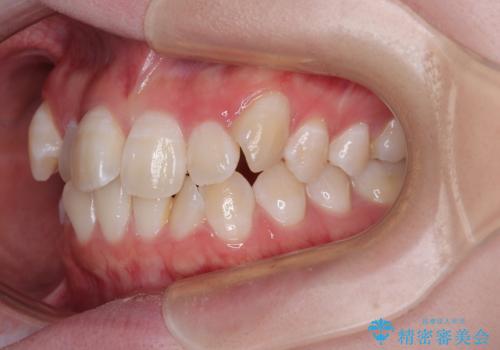

- 「前歯のデコボコ(叢生)をきれいに整えたい」とのことでご来院されました。

マウスピース矯正も検討されていましたが、「装着時間の自己管理が難しそう」「なるべく早く治療を終えたい」とのご希望から、ワイヤー矯正を選択されました。